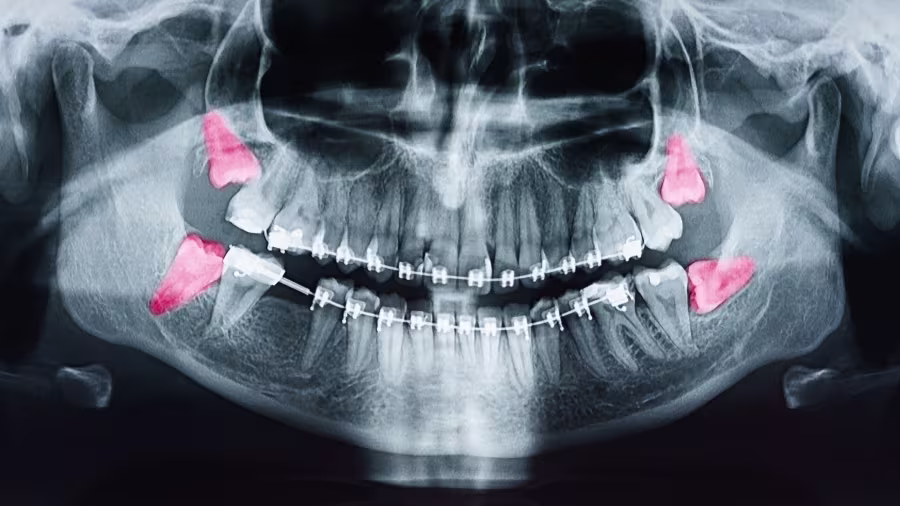

Consultation and Digital Imaging

We use 3D CT scans to assess the exact position and root structure of your wisdom teeth, so there are no surprises.